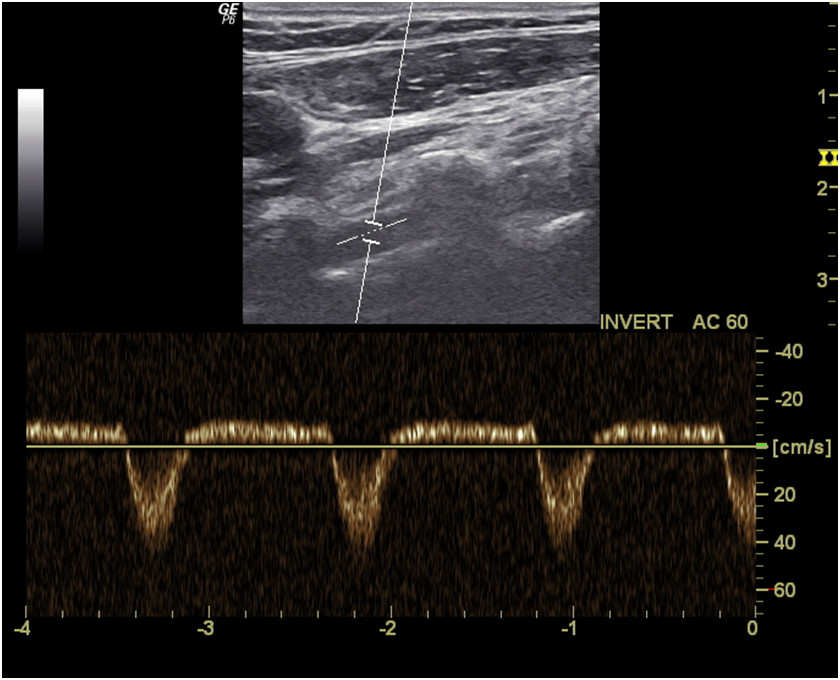

Pacjent zgłasza okresowe występowanie zawrotów głowy, szczególnie podczas prac fizycznych wykonywanych rękami. W badaniu przedmiotowym nie stwierdzono istotnych odchyleń od normy. Nie stwierdzono różnic w wyczuwaniu tętna na kończynach górnych ani też objawów ucisku w obrębie górnego otworu klatki piersiowej. Pacjenta skierowano na badanie dupleksowe tętnic szyjnych

i kręgowych. Oceniając prawą tętnicę kręgową stwierdzono obecność spektrum przedstawionego na poniższej rycinie. U pacjenta można podejrzewać: